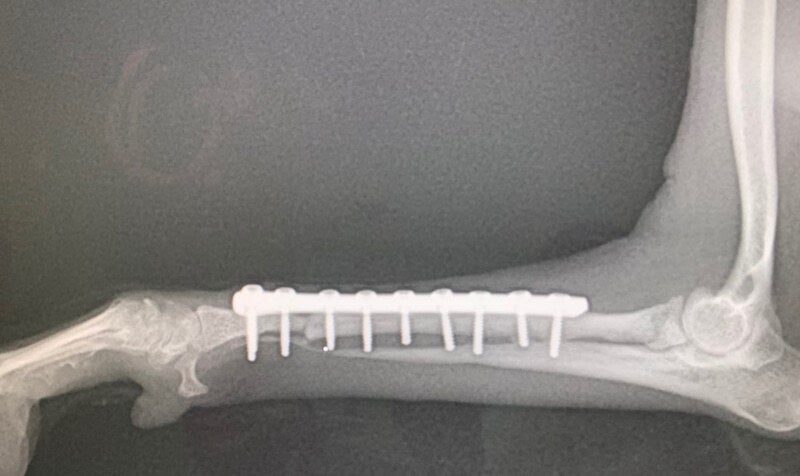

両前脚骨折で保護され、2ヶ月前にまずは右前脚を手術した、いちごちゃん。

骨がかなり細く中々繋がらなかったのですが、2ヶ月経過しやっと癒合してきました。

細い骨はほぼ癒合しており、太い骨も上部が癒合してきているような影が見えます。

いちごちゃんは術後から元気一杯でしたが、コルセットの脚は中々地面に付かずに、ずっと3本足で生活していました。

今までずっと3本足での生活だったので、慣れなかったのだと思います。

何度目かの検診時にコルセットが外れ、それ以降は右前脚も今までより使えるようになってきて、4本足で歩く姿をよく見かけるようになりました。

今はまだリハビリ期間でお散歩も50m位と言われていますが、もっと歩きたそうにしているようです^_^

まだ、左前足の手術も必要ですが、いちごちゃんのリハビリの経過を見ながらとなります。